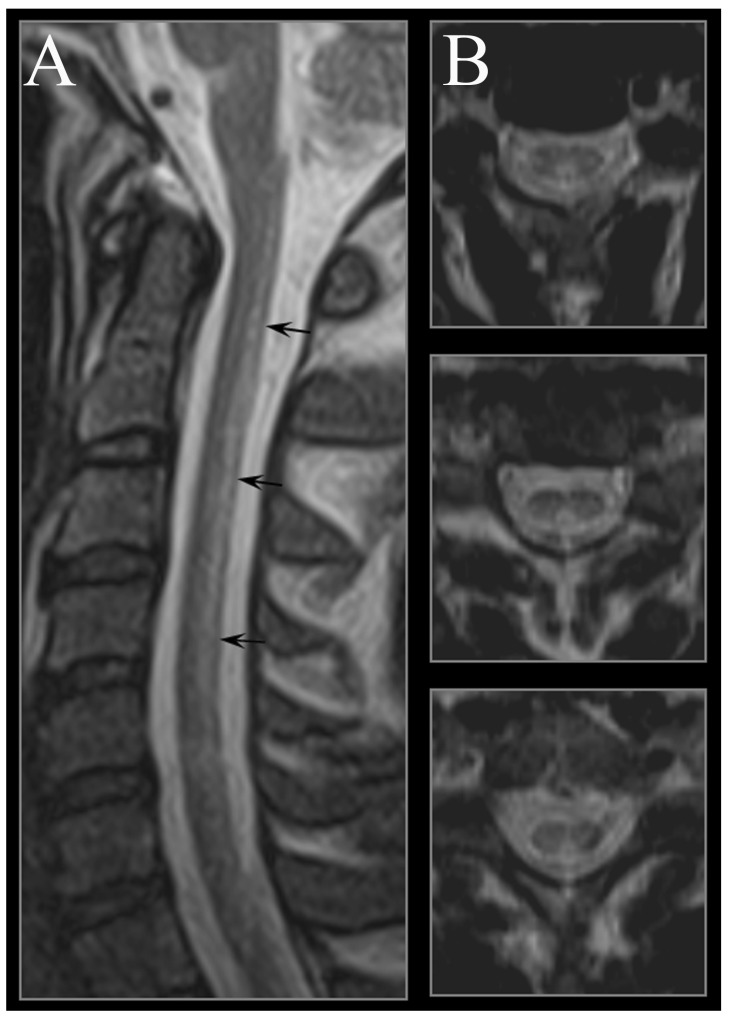

- 画像 CTですりガラス陰影,メロンの皮様,crazy-paving shadow(不揃いな敷石状)